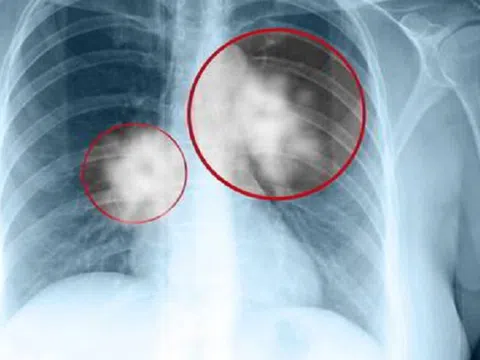

U nang phổi có phải là ung thư không?

U nang phổi là hiện tượng mô hoặc tế bào phổi phát triển bất thường, dẫn đến hình thành khối u tại phổi. Phần lớn các khối u này là lành tính, nhưng người bệnh vẫn cần phải kiểm soát và theo dõi định kỳ theo hướng dẫn của bác sĩ chuyên khoa.